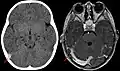

Синус-тромбоз при нативной компьютерной томографии (сагиттальная реконструкция) Синус-тромбоз при нативной компьютерной томографии (слева) и МРТ в режиме T1 с контрастным усилением (справа)

Синус-тромбоз при нативной компьютерной томографии (слева) и МРТ в режиме T1 с контрастным усилением (справа)